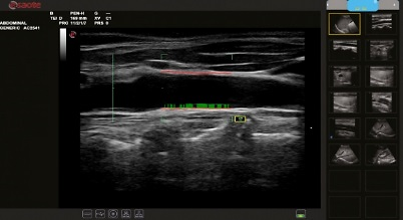

Bi-rads, Ti-rads protocol – Classify Breast, Thyroid focal node become simple, fast and precise with the support of automatical assessment program followed by ACR standard (American College of Radiology).

Realtime QIMT – Automated real-time detection of Intima Media Thickness, including standard deviation and reliability index, based on unique technology – RF signal analysis.